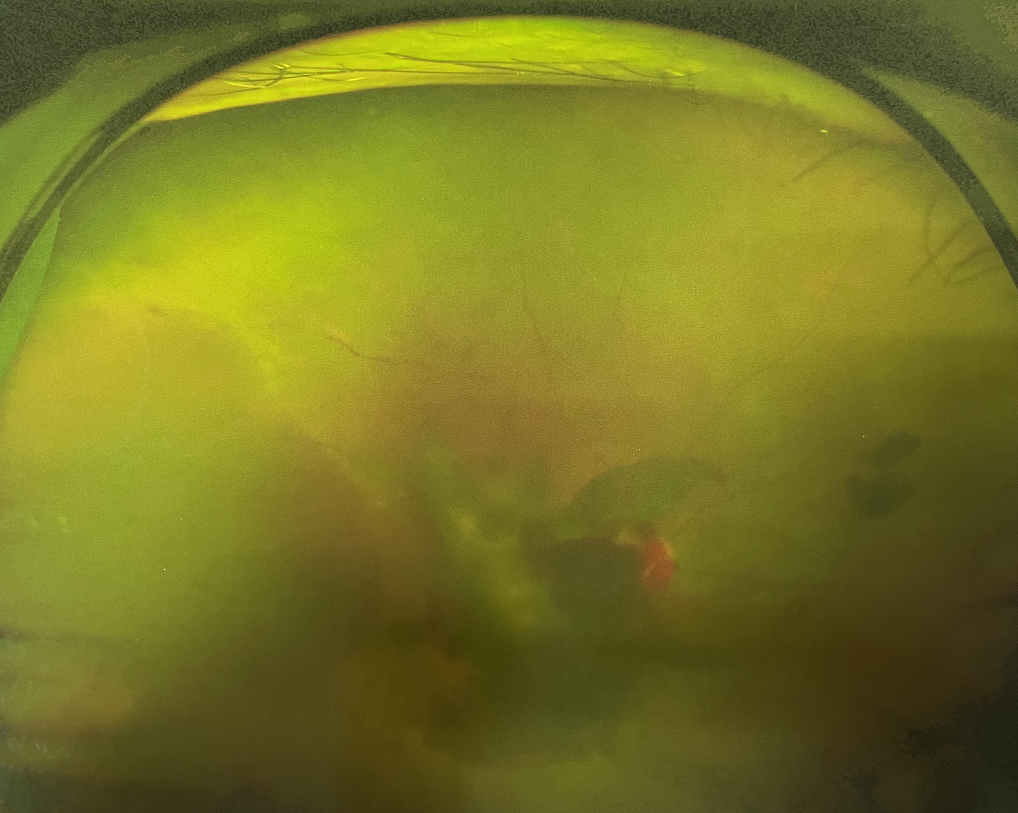

眼底出血不是獨(dú)立的眼病,而是由于眼球自己的病變和某些全身疾病的并發(fā)癥導(dǎo)致眼底的視網(wǎng)膜或脈絡(luò)膜出血,如果出血量大就會(huì)進(jìn)入到眼球的玻璃體內(nèi),從而影響視力,如果沒(méi)有得到恰當(dāng)?shù)闹委熆蓭?lái)更嚴(yán)重的并發(fā)癥造成失明。

眼底出血的患者,如果出血量少,而且在視網(wǎng)膜周邊部可能沒(méi)有明顯癥狀,患者僅感到眼前有黑影浮動(dòng);如出血量多,將嚴(yán)重影響視力,甚至完全被黑影所遮擋僅剩光感;如出血位于視網(wǎng)膜的黃斑區(qū),患者視野中心區(qū)被暗影遮擋,周邊尚有部分視力。

先是散瞳檢查眼底,可以明確眼底出血的性質(zhì),出血部位和出血量有多少。眼B超檢查,對(duì)于眼底出血量特別多,無(wú)法看清眼底的患者,就需要進(jìn)行眼部B超檢查,以了解出血量,出血部位、有無(wú)合并視網(wǎng)膜脫離;還可以明確是否患有視網(wǎng)膜或脈絡(luò)膜的腫瘤。